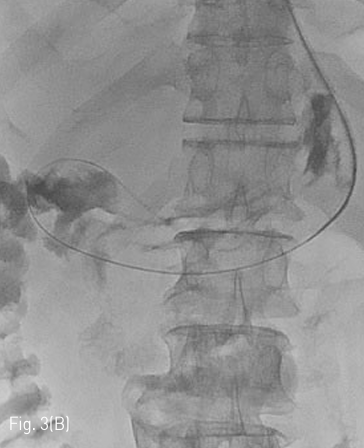

경피적 영상유도 위창냄술을 시행하기 위해 시술 전 촬영한 복부 컴퓨터단층촬영을 검토하였고, 환자는 간경화로 다량의 복수가 있고, 접근 경로에 문맥 전신 곁가지들로 인한 확장된 혈관들이 관찰되었다 (Fig. 1). 경피적 영상유도 위창냄술을 시행하는 것이 어렵다고 판단하였고 환자에게 Percutaneous transesophageal gastrostomy (PTEG)를 시행하기로 결정하였다.

Fig 1A

Axial (A) and coronal (B) CT shows large amount of ascites and tortuous dilated vessels between abdominal wall and stomach at access route.